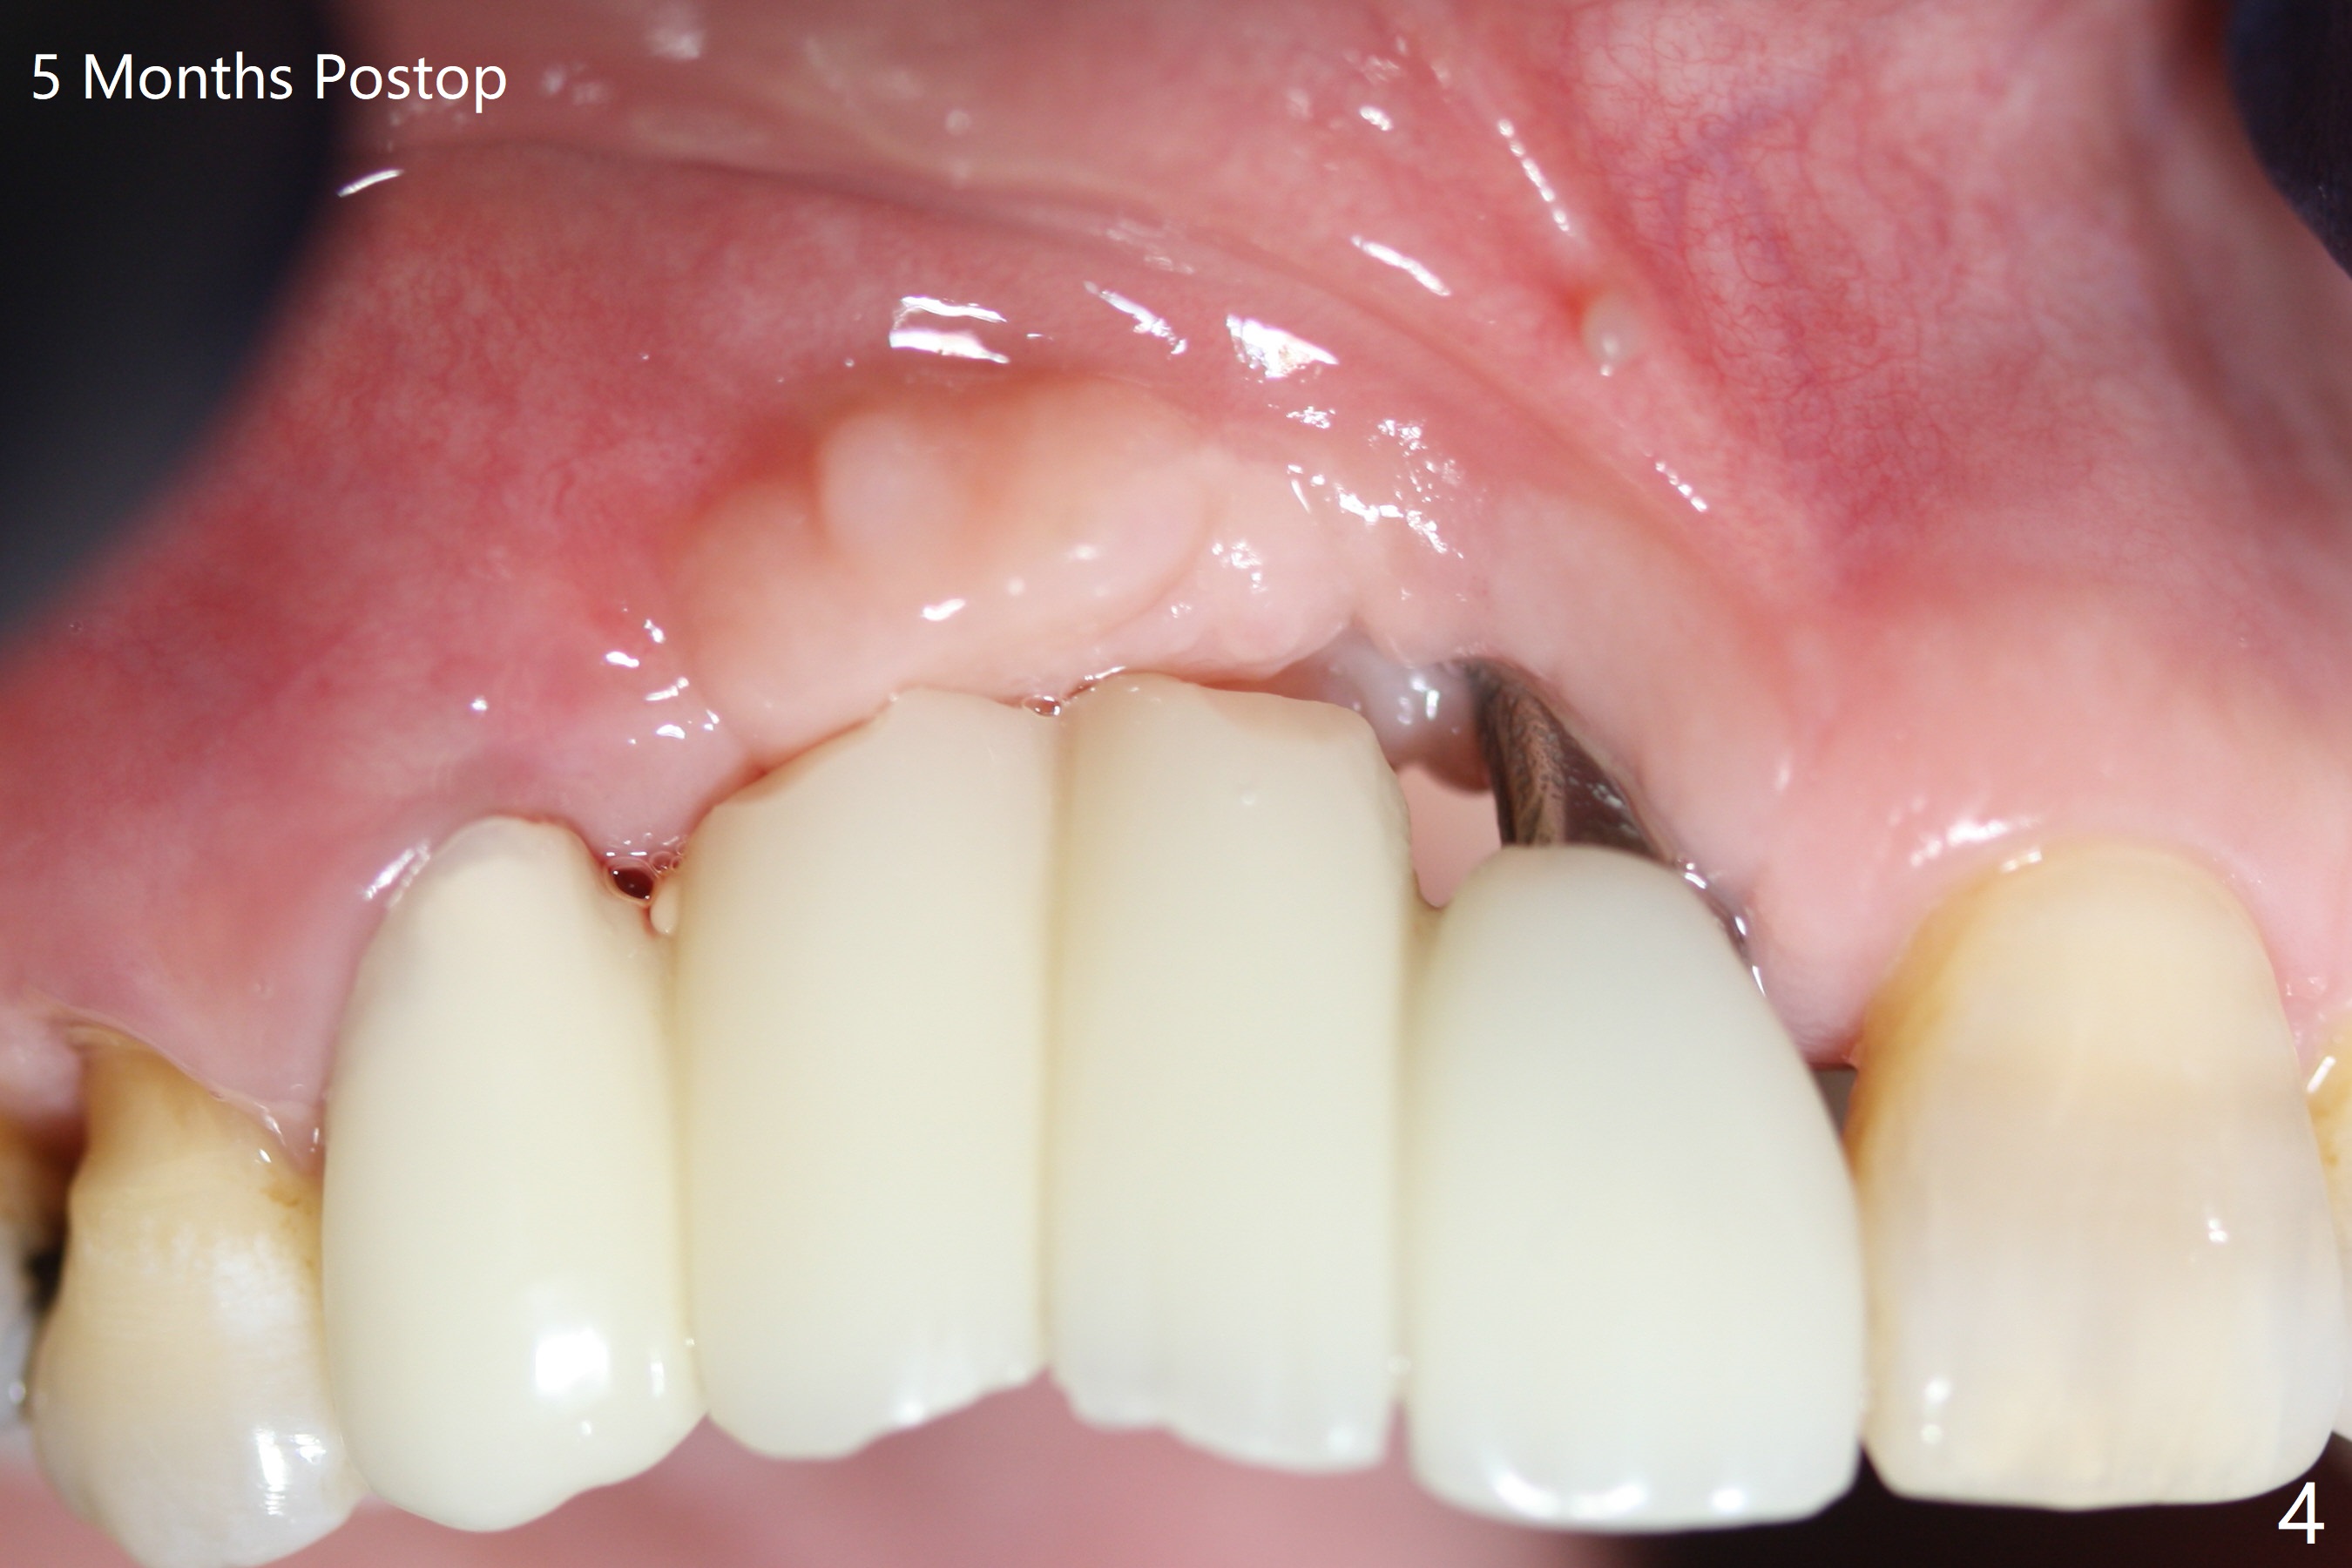

Narrow Implants at #6 and 7

Four months post bone graft with tenting screws at #6 and 7 and implant re-placement at #8, the ridge at #6 and 7 appears to widen slightly, appropriate for narrow implants (Fig.1,2). Guide will be fabricated. The implant at #8 seems to have osteointegrated (Fig.3) with distal gingival recession (Fig.4). One year 5 months later, the tooth #5 is infected with apparently mesial bone loss (Fig.5 *) and papillary erythema and edema (Fig.6). However the pockets are not deep. A gingival embrasure is created between #5 and 6 for self cleansing. The latter does not work. Implants will be placed at #5 and 7 (Fig.7,8).